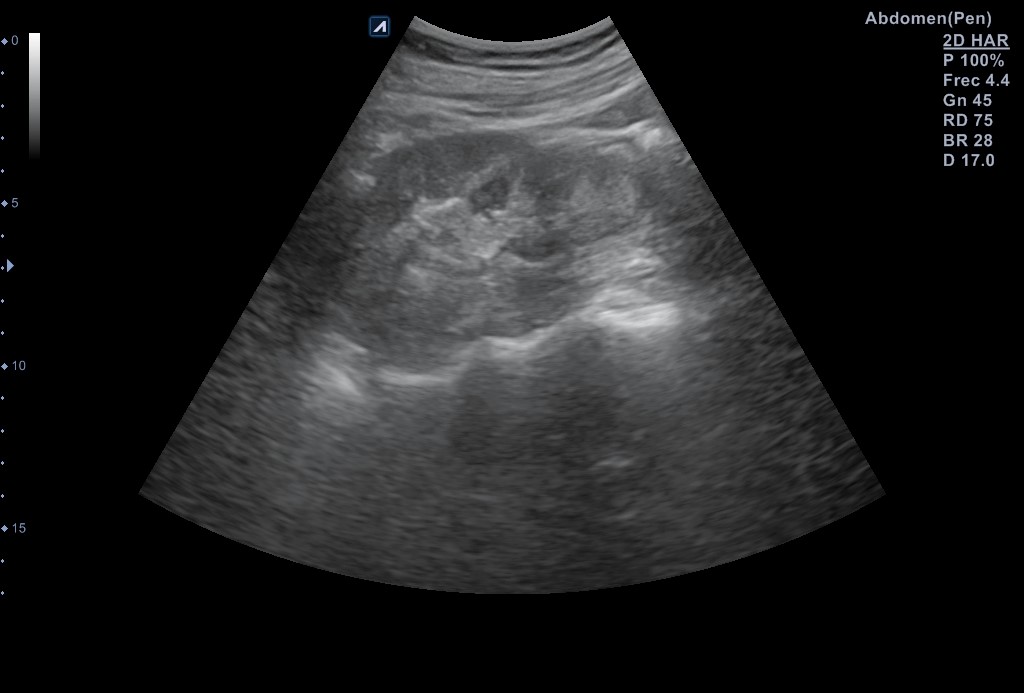

Se reevalúa a la paciente en consulta 2 semanas después, que refiere mejoría sintomática. Se repite la ecografía evidenciándose imágenes de riñón izquierdo sano y ausencia de la lesión previamente descrita.